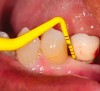

The mucosa surrounding the implant should be evaluated for clinical signs of inflammation such as redness, erythema, and inflammation, which can be assessed by bleeding on probing (Figure 1).4,5 Several gingival indices have been modified for their application around implants.6,7 Difficulties in recording mucosal inflammation have been reported, such as non-keratinized peri-implant mucosa normally appearing redder in color than keratinized tissue.8,9

Figure 1. Peri-implant soft-tissue evaluation: peri-implantitis. Note redness, erythema, and inflammation of peri-implant soft tissue.

Figure 1